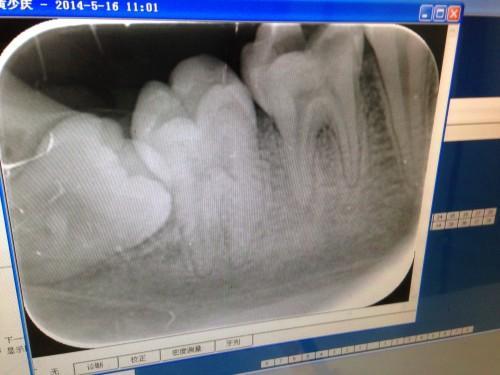

补牙拍片多久可以怀孕

补牙是一件非常麻烦的事情,因为要涉及到部分药物,同时还会影响正常的进食,补牙的方法也有很多种,但是对于在备孕期间的孕妈妈来说,补牙的问题一直是非常重要的。那么,补牙拍片多久可以怀孕呢?